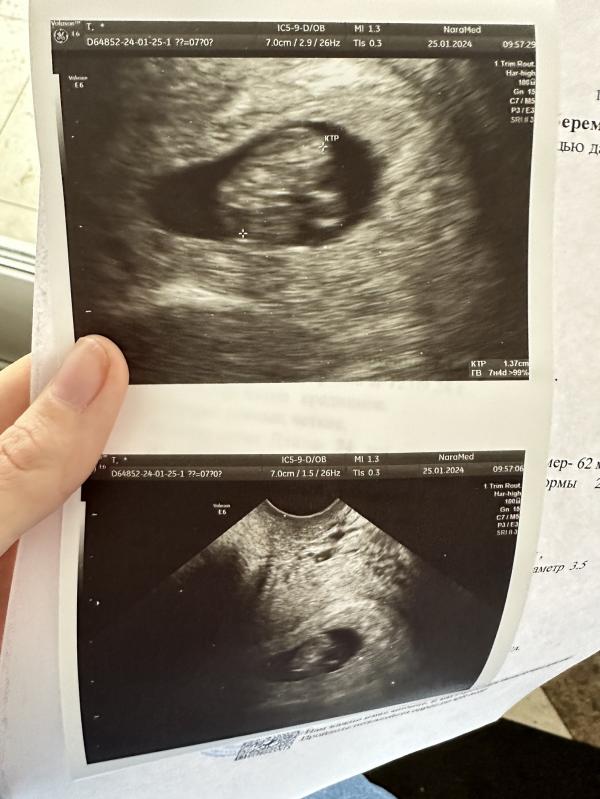

УЗИ показало, что котенок вырос за 10 дней! Срок беременности по УЗИ больше, чем по месячным. Что делать?

Сходила на узи, котеночек вырос так сильно за 10 дней🥹

По месячным 7 недель, по УЗИ 7 недель 4 дня🫶🏻